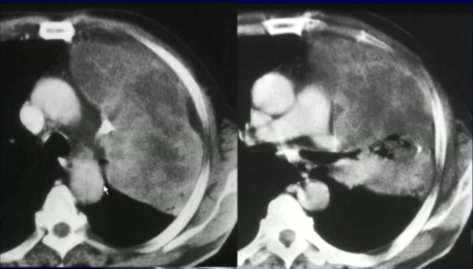

图5 克雷伯氏肺炎。中间可见有很多低密度改变,边界清楚,未越过叶间裂,肿瘤可以越过叶间裂,但炎症不太容易越过。